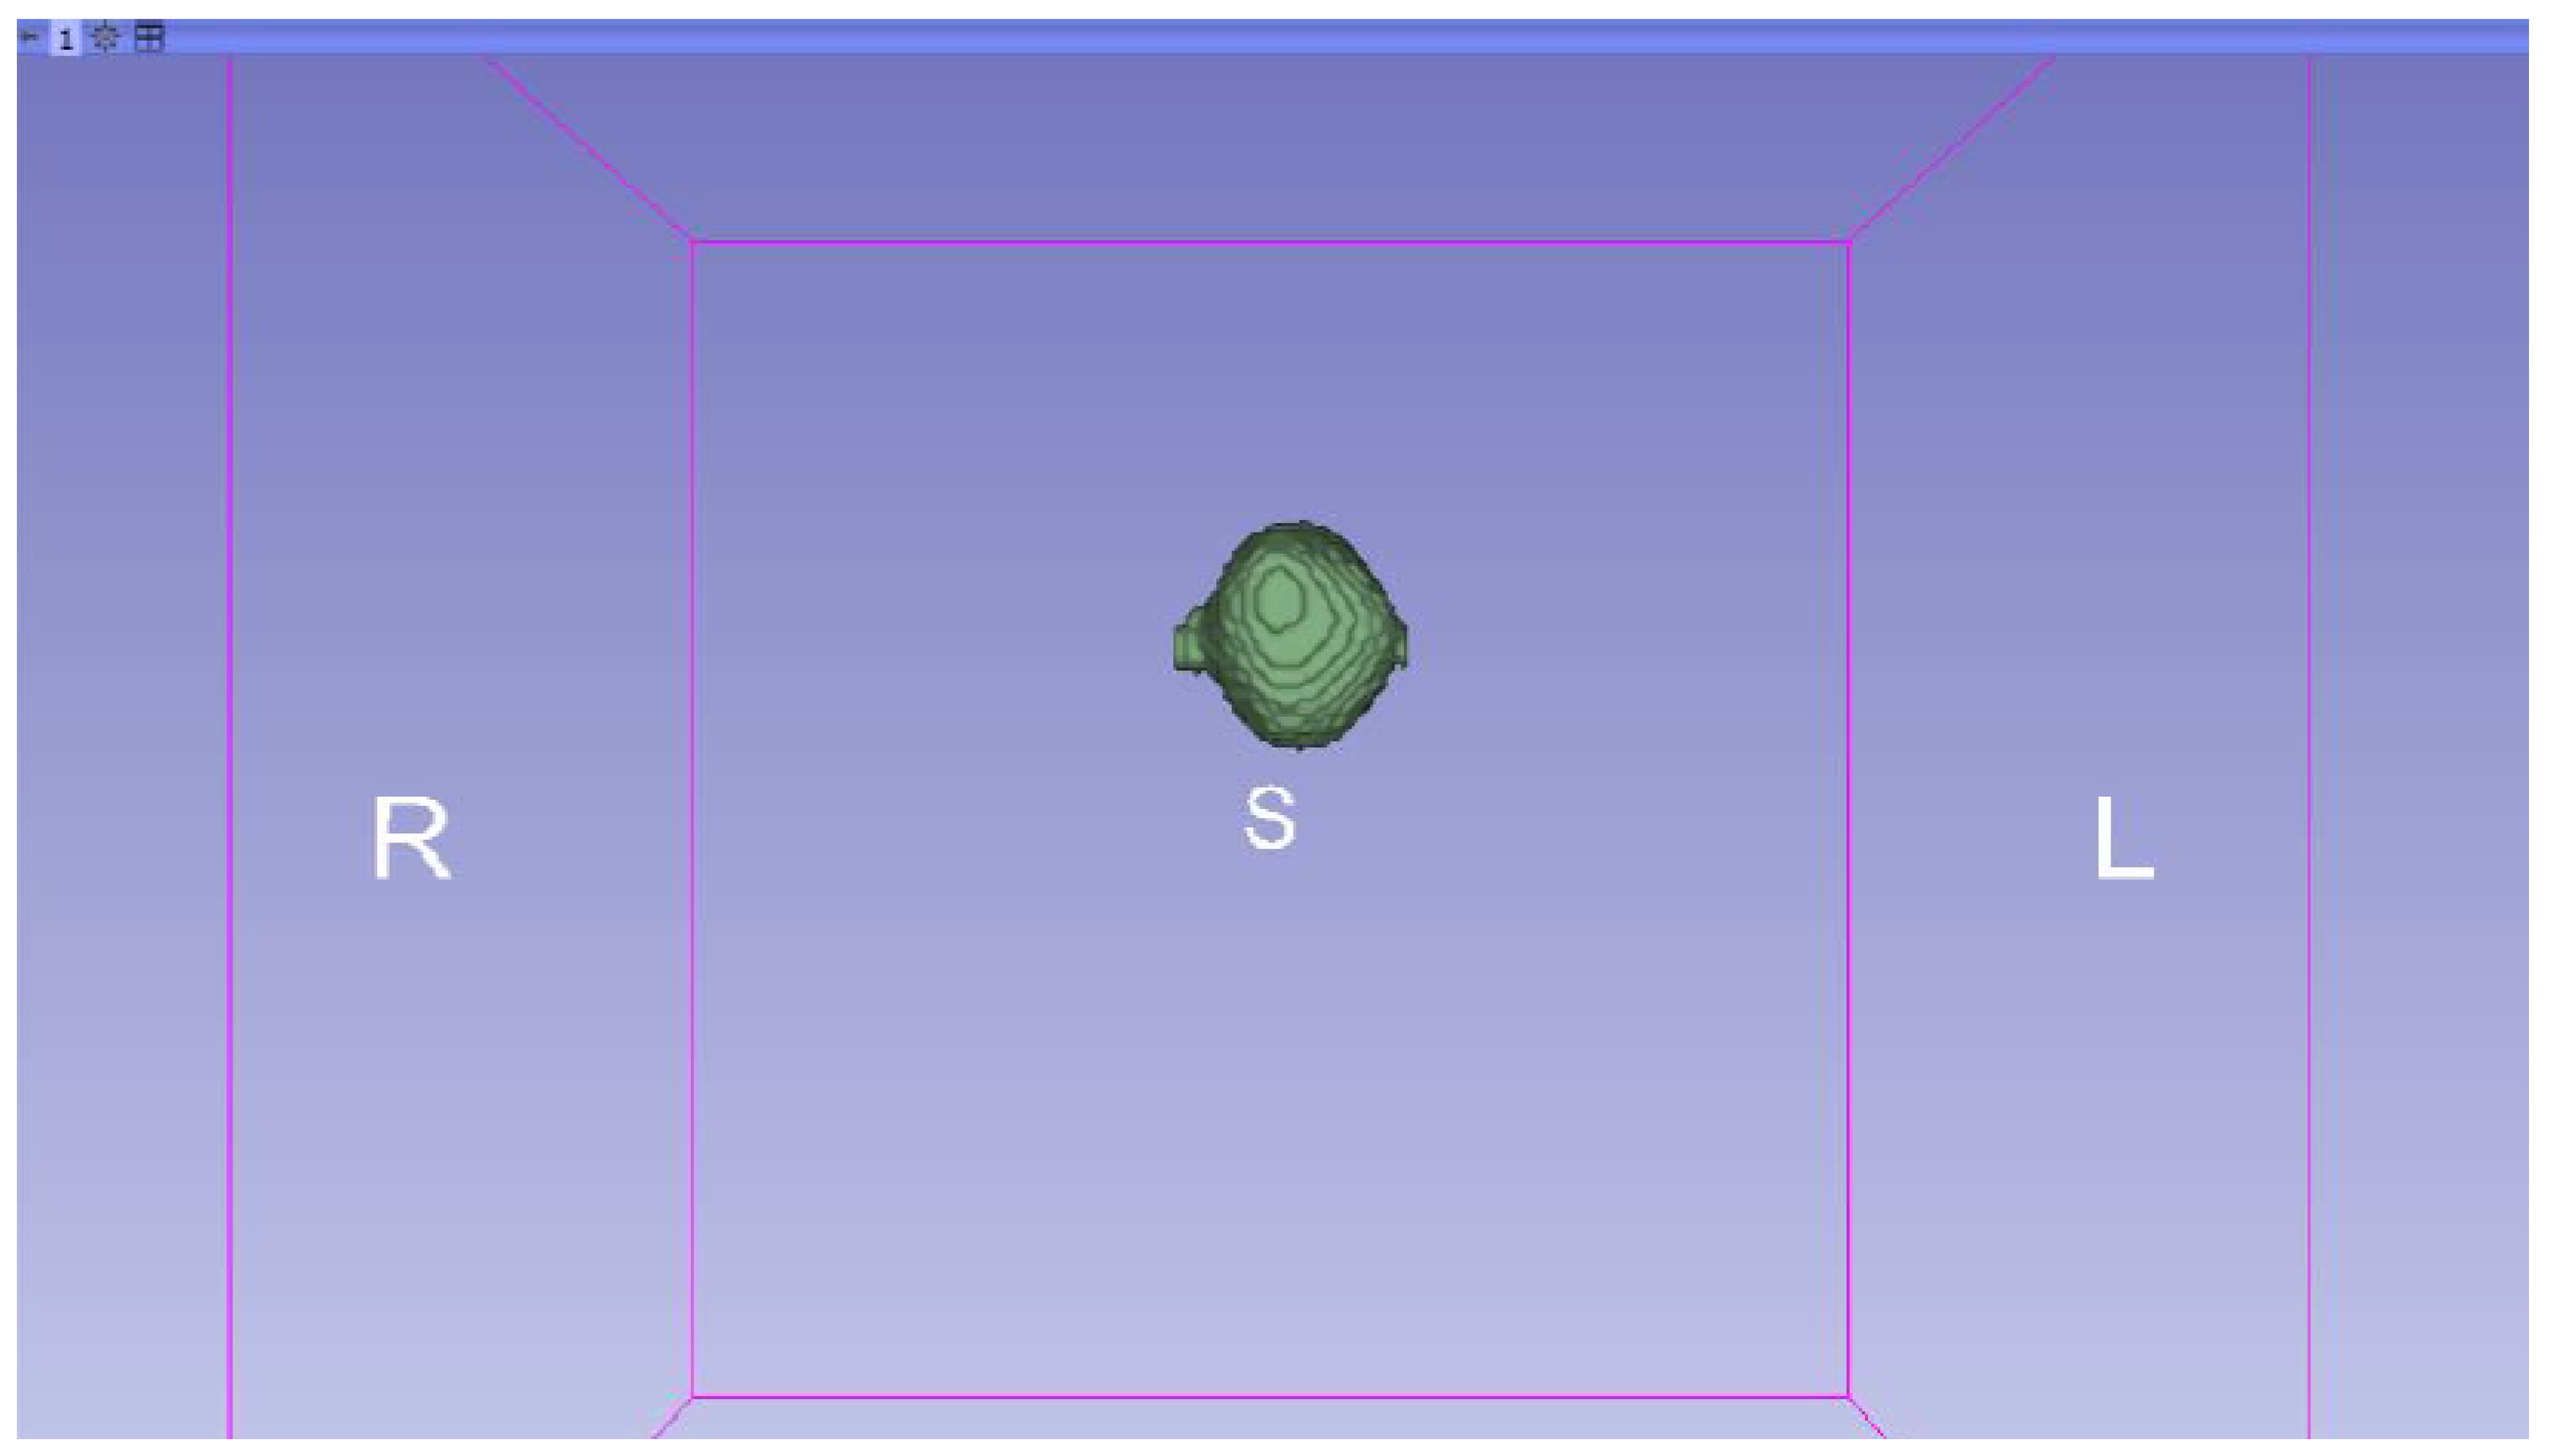

3.3. Human Brain Tumour

3.3.1. DICOM-to-STL Files